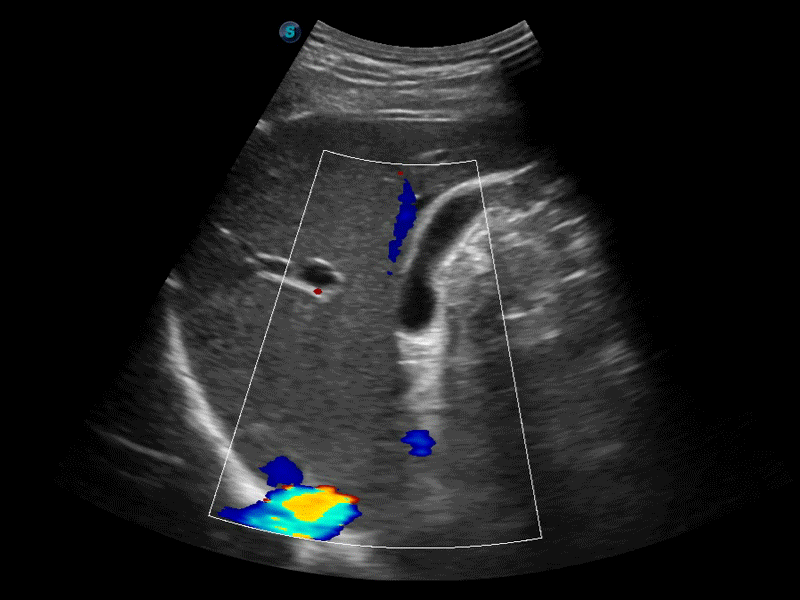

高分辨率血流成像技術提高了對低速血流信號的檢測能力。在提高空間分辨率的同時,也克服了血流外溢現象,為用戶提供更加真實的血流動力學信息。